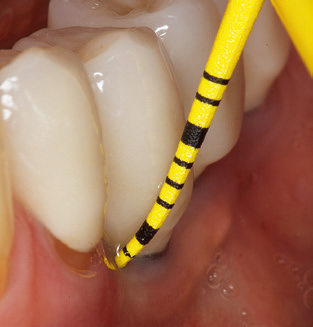

Das aktuelle Arbeitskonzept für die UPT

Abb. 4: Für das Sondieren an dentalen Implantaten sind biegsame, millimeterskalierte Sonden empfehlenswert (z.B. Colorvue Kit PCV11KIT6, Hu-Friedy). – Abb. 5a und b: Eine gerade Arbeitsspitze (1P, W&H Dentalwerk Bürmoos GmbH) ist universell für die Instrumentierung natürlicher Zähne geeignet. – Abb. 6: Für die Bearbeitung schwer zugänglicher Bereiche der Zahn- und Wurzeloberflächen (z.B. Furkationen) bieten sich gebogene Arbeitsspitzen (3Pr/3Pl, W&H Dentalwerk Bürmoos GmbH) an. – Abb. 7: Die spitz zulaufende sechseckige Implantatreinigungsspitze (1I, W&H Dentalwerk Bürmoos GmbH) ermöglicht eine atraumatische und effiziente Reinigung der Kronen- und Abutmentoberflächen. – Abb. 8: Für die manuelle Instrumentierung der Implantatoberflächen sind Titan- oder Carbonküretten geeignet.